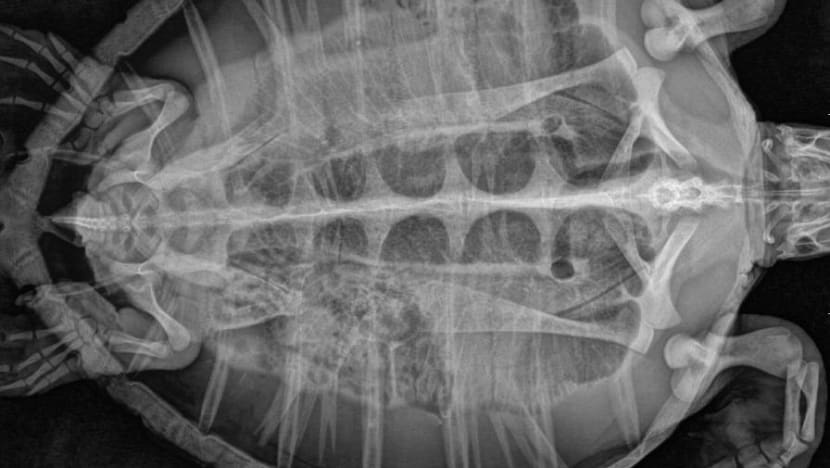

The turtle, named Tuk by veterinarians, was weak, could not eat by itself and had trouble swimming. Subsequent examinations and X-rays revealed that it had ingested a shocking amount of plastic bags, hard plastic, cloth and other trash, which were obstructing the turtle’s gastrointestinal tract but were later defecated.

“We were surprised. This is the first sea turtle that had ingested more than 300 pieces. Normally we have sea turtles that have ingested 10 or 20 pieces. This one is like, wow,” said Araya Boonkasemsanti, the marine veterinarian caring for Tuk at PMBC.

“If the X-rays show no impaction, then she can go back into the wild,” she said, referring to the possibility of a mass of stool that can’t be pushed out by the turtle.